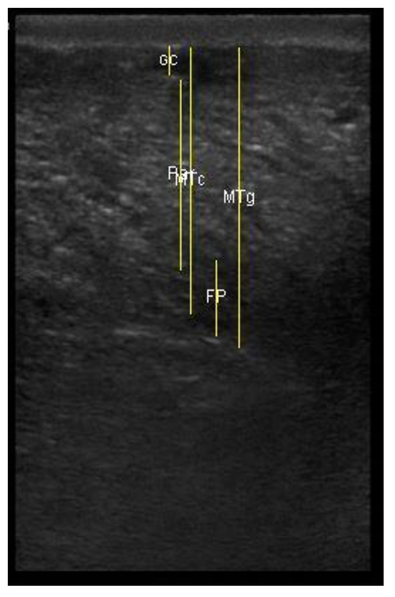

| 113 days of pregnancy (P113) Scanning depth 4.7 cm | ![]() | ![]() | MT generous: 28.9 mm MT conservative: 25.9 mm Gland cistern: 3.3 mm Parenchyma: 10.9 mm Fat Pad: 10.0 mm |

| 109 days of pregnancy (P109) Scanning depth 4.7 cm | ![]() | ![]() | MT generous: 36.8 mm MT conservative: 27.2 mm Gland cistern: 4.7 mm Parenchyma: 15.4 mm Fat Pad: 5.5 mm |

| 107 days of pregnancy (P107) Scanning depth 4.7 cm | ![]() | ![]() | MT generous: 31.7 mm MT conservative: 22.3 mm Gland cistern: 4.5 mm Parenchyma: 8.3 mm Fat Pad: 7.8 mm |

| 107 days of pregnancy (P107) Scanning depth 4.7 cm | ![]() | ![]() | MT generous: 32.2 mm MT conservative: 25.3 mm Gland cistern: 3.6 mm Parenchyma: 12.4 mm Fat Pad: 7.9 mm |